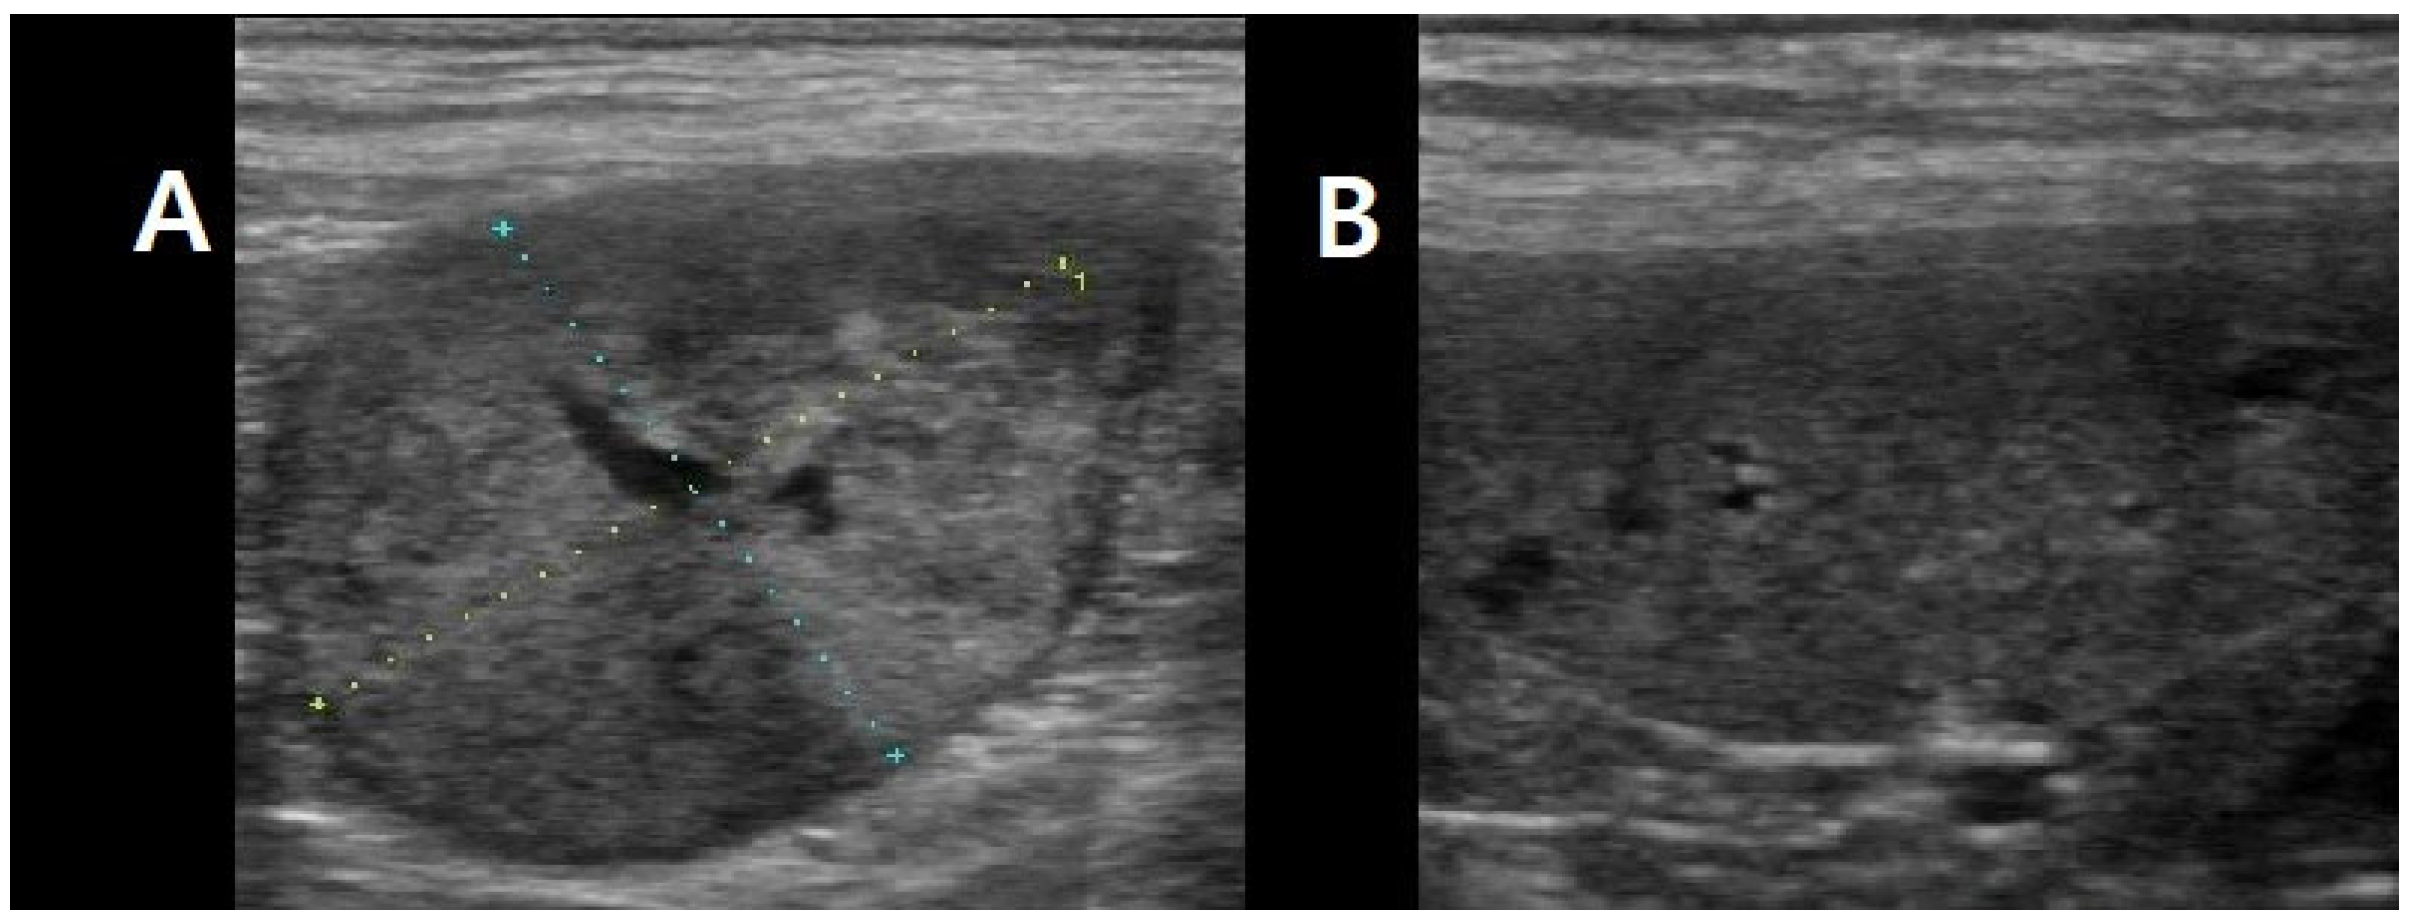

Laboratory analyses revealed a marked increase in canine C-reactive protein (cCRP, 95.4 mg/L; reference range: <20 mg/L) and canine pancreatic lipase (cPL, 975 μg/L; reference range: <200 μg/L). The complete blood count (CBC) demonstrated moderate leukocytosis (23.5 × 109/L; reference range: 6.0–17.0 × 109/L) characterized by neutrophilia (14.8 × 109/L; reference range: 3.0–11.5 × 109/L). All other hematologic and biochemical parameters were within normal limits. Thoracic radiography and abdominal ultrasonography identified an uncharacterized left retroperitoneal mass measuring approximately 3 × 2 cm in diameter, in addition to a splenic mass (Figure 1).

Figure 1. Ultrasonographic images of abdominal tumors. (A) An unidentified left retroperitoneal mass (approximately 3 × 2 cm in diameter). (B) The spleen.